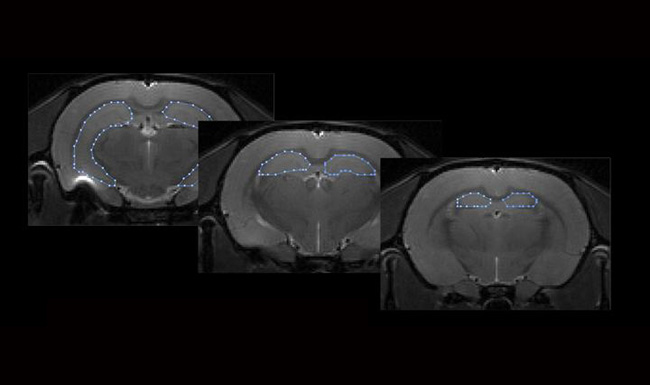

Even A Brief Period Of Stress Could Affect Memory: Study

Aside from memory loss, the hippocampus or 'memory center' in the brains of rats shrank after just three days of chronic stress.